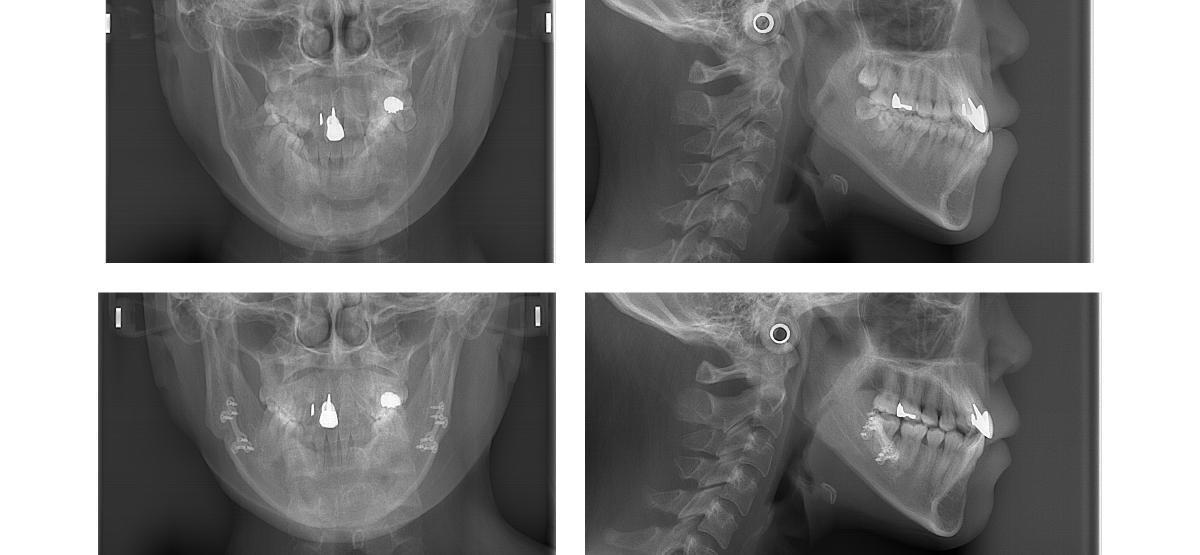

①顎矯正手術(外科矯正)の矯正治療例(20代女性・治療期間2年)

| 年齢・性別 | 20代女性 |

| 治療期間 | 2年 |

| 抜歯 | なし |

| 治療費 | 100万円(調整費、保定費まで含む総額制) |

| 備考 | 裏側矯正 |

| リスク・副作用 | 痛み・治療後の後戻り・歯根吸収・歯髄壊死・歯肉退縮 |

川崎市からご来院の20代女性で、受け口(反対咬合)と交叉咬合(すれ違い)の症状がありました。

治療法は裏側矯正(舌側矯正)で、治療期間は2年です。

非抜歯で矯正治療を行い、キレイな歯並びになりました。